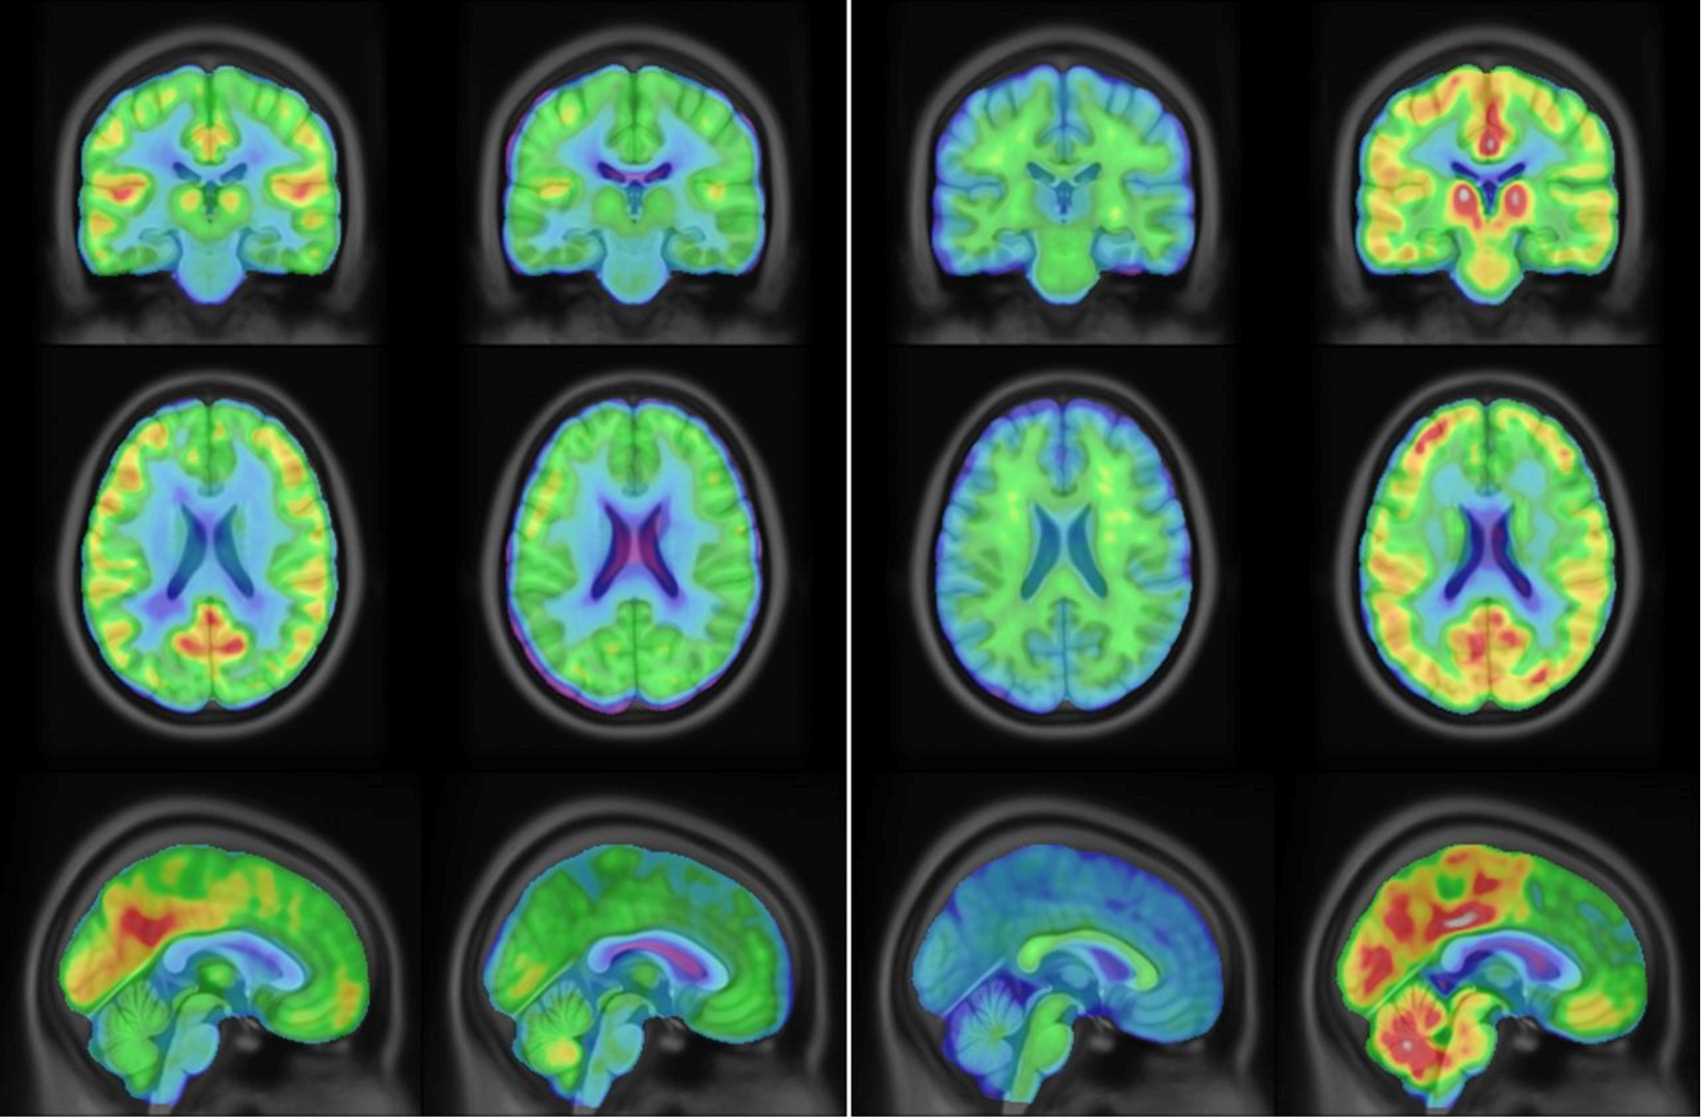

Radiologic Science is a broad term that refers to medical imaging and radiation therapy professionals who use technologies such as ultrasound and x-ray equipment or linear accelerators to diagnose or treat patients. These professions require the ability to acquire technical skills and understanding while also developing excellent communication abilities to work with patients and healthcare team members from diverse backgrounds.

Radiologic Technicians use these techniques to diagnose diseases like cancer, detect broken bones or find foreign objects in the body.

Sonographers use ultrasound, or high-frequency sound waves, to identify and diagnose diseases in body organs and tissues.